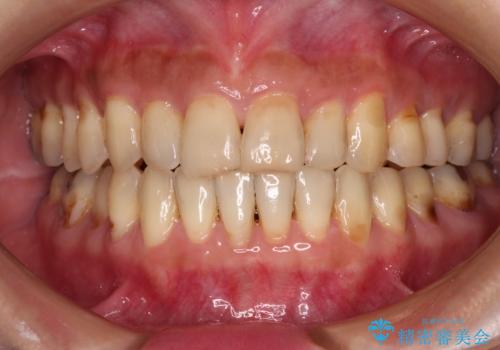

- 上の前歯の出っ歯とでこぼこの歯並びを気にして来院された患者様です。

上下顎歯列ともに前方に突出していましたが、上顎歯列がより前方位にあったため、上顎左右は第1小臼歯を、下顎左右は第二小臼歯を抜歯することとしました。

目立たないワイヤー装置にて抜歯矯正を行うこととしました。

下顎は過剰歯が埋伏しており、それが原因となってスペースが閉じなかったため、途中で抜歯して速やかに仕上げました。